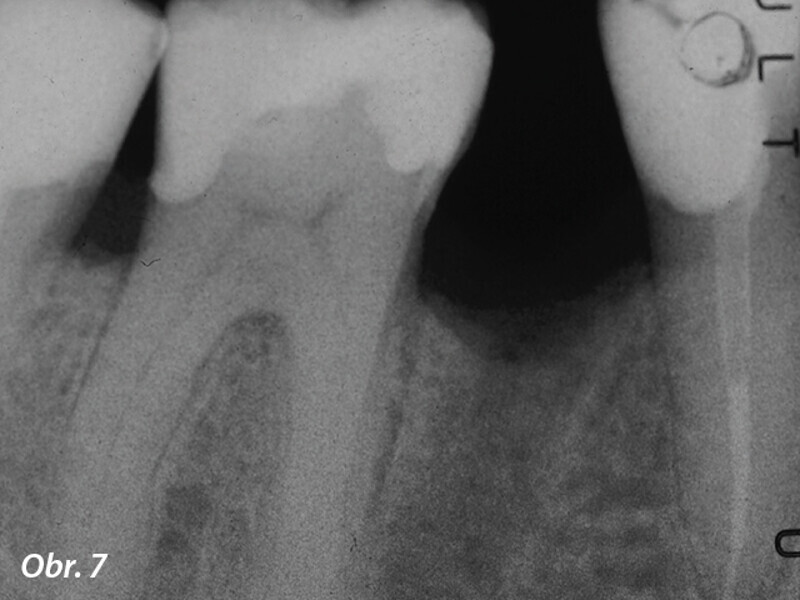

3D technologie v diagnostice a léčbě endodontických onemocnění